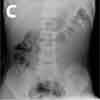

Figures A, B, and C track the course of a 1½-inch tack traversing the GI tract of a 2-year-old. With the exception of straight pins, sharp foreign bodies increase the complication rate associated with ingestions from less than 1% to about 25%. Straight pins usually follow a benign course, unless multiple pins have been ingested.

In this patient's case, serial abdominal radiographs followed the tack along a predictable path. It was expelled with no complications within 24 hours.